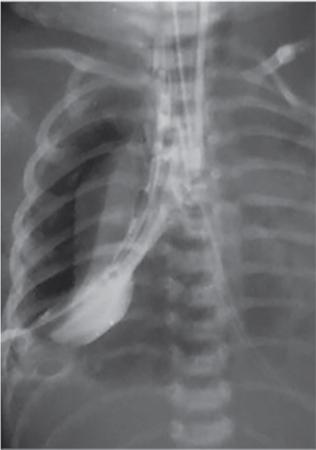

C.V. Kanimozhi, S. Muralinath, Raveendran J. Many of the important congenital gastrointestinal abnormalities present acutely in the newborn; some present much later. These include obstructive gastrointestinal lesions that present with vomiting, abdominal distension and not having passed meconium. The imaging modalities that are most commonly used in the evaluation of neonatal gastrointestinal abnormalities are plain films, contrast studies and ultrasound. Plain films remain a valuable tool in the assessment of abdominal abnormalities in the neonate. They are also an excellent guide to determining the next proper imaging study to perform for a particular problem. Certain neonatal bowel disorders have a pathognomonic appearance on radiographs obviating the need for further imaging. The essential and basic view to be done at the bedside is the supine view of the abdomen. In the evaluation of abnormal intra-abdominal gas patterns, alternative decubitus views, prone and supine cross-table lateral views may be taken. Erect view is not utilized in neonatal practice at the bedside as it is impossible to restrain a neonate in that position and unnecessarily subjects the neonate to stress, which may worsen the condition of an already sick baby. Evaluation of the bowel gas pattern and the anatomic localization of the intra-abdominal gas is the key to diagnosis in the evaluation of diseases of the GI tract. The bowel gas in the neonate is essentially swallowed air (Box 7.8.1). Movement of Air Through the GIT in a Term Neonate Most infants pass meconium by 24 hours of life. In order to interpret the bowel gas pattern and determine if an abnormality is present, it is crucial to know the age of the neonate (hours since birth) at the time the radiograph was taken. When there is impaired swallowing, such as due to CNS depression or in prematurity, radiographs show diminished bowel gas. In cases of bowel atresia, radiographs show absence of bowel gas in distal segments. Thus, the distribution of bowel gas and its pattern serve as pointers to the diagnosis. After the radiograph has been done, depending on the findings, an ultrasound or fluoroscopic contrast study may be performed next. The radiologist should tailor the contrast study to suit the particular patient and the clinical question that needs to be answered. In cases of suspected high GI obstruction, an upper GI contrast series is study of choice; in cases of suspected low GI obstruction a contrast enema should be performed to delineate the anatomy. When performing fluoroscopic studies, it is important to bear in mind the radiation dose and to adopt the ALARA principle. Minimizing radiation exposure in children is important because they are more sensitive to the effects of radiation and have a longer life expectancy than adults. The technical parameters must be adapted to paediatric imaging. Ultrasound is a useful bedside tool particularly in the sick neonate. In neonates, the sonographic image resolution is excellent due to the lack of significant body fat. In neonates, exquisite images of the abdomen can be obtained with the high-resolution ultrasound probe, which permits imaging the bowel wall in great detail. In addition, it can also reveal other causes for abdominal distension or vomiting. In this chapter, we will discuss the aetiology, clinical presentation and imaging appearances of congenital neonatal gastrointestinal abnormalities. We will also discuss common acquired abnormalities that present in the neonatal period, namely necrotizing enterocolitis. Congenital oesophageal malformations of the newborn include the various types of atresia (with and without fistula) and oesophageal duplications. Oesophageal atresia with or without tracheoesophageal fistula (TEF) is a common congenital anomaly that manifests in the neonatal period. It is also the most important congenital malformation of the oesophagus. Oesophageal atresia is commonly associated with other anomalies of the gastrointestinal tract such as imperforate anus, pyloric atresia, duodenal atresia and annular pancreas and less frequently with anomalies of the cardiac and genitourinary systems. About 20% of patients with oesophageal atresia have the VACTERL syndrome (vertebral anomaly, anorectal atresia, cardiac lesion, tracheoesophageal fistula, renal anomaly, limb defect). Oesophageal stenosis and webs may be associated with oesophageal atresia. The aetiology of oesophageal atresia and TEF is not completely understood. Faulty separation of the primitive trachea and oesophagus is the most widely accepted theory. The way the primitive foregut cleaves into a ventral (tracheal) passage and a dorsal (oesophageal) passage is a complex process and is poorly understood. Folds developing from the longitudinal ridge is said to separate the two. When the separation has an extreme tracheal bias, an oesophageal atresia occurs and if the bias is towards the oesophagus, then a tracheal atresia ensues. Incomplete separation may result in fistula of various types. Oesophageal atresia and TEF are classified depending upon the absence or presence and location of the fistula between the oesophagus and the trachea (Fig. 7.8.1). Neonates present within a few hours of birth with excessive salivation, drooling, cyanotic spells and regurgitation of feeds. The inability to successfully pass a nasogastric tube strongly suggests oesophageal atresia. Newborns with H-type fistula may have feeding difficulties and choking, but often the presentation and diagnosis is only later in infancy when the patient presents with cough, choking episodes and recurrent pneumonia. The role of imaging is to diagnose, define the anatomy to the best extent possible and evaluate for other anomalies to provide a clear picture for the paediatric surgeon. For example, it is important for the surgeon to know the side of the aortic arch in order to lateralize the surgical approach. Chest X-ray and Echo can localize the arch and determine if an anomalous right-sided aortic arch is present. Plain films of the chest including abdomen need to be obtained. The radiograph will demonstrate the air-filled distended proximal oesophageal pouch. If a nasogastric tube has been inserted, the coiled tube will be seen within the pouch. Absence of bowel gas in the abdomen indicates oesophageal atresia without a distal fistula – types A and B have this radiographic appearance (Fig. 7.8.2). The presence of gas in the gastrointestinal tract indicates the presence of a distal fistula – types C and D (Fig. 7.8.3). Contrast studies to delineate the proximal pouch are generally not indicated. Coiling of the nasogastric tube in the proximal pouch confirms the diagnosis. Chest radiographs frequently show changes of consolidation due to aspiration pneumonia, most often involving the right upper lobe (Fig. 7.8.4). In cases of H-type fistula, plain films are nonspecific and the diagnosis depends on contrast studies. Radiological diagnosis is made by means of a tube oesophagogram. This study has the potential risk of aspiration and the neonate may desaturate quite rapidly. Hence, it is important to have neonatal emergency resuscitation at hand. The tube oesophagogram is performed under fluoroscopy with the baby in lateral- or steep-prone oblique position. The NG tube is placed at the oesophagogastric junction and is gradually withdrawn while simultaneously injecting contrast. Nonionic low-osmolar contrast agent should be used. Most of the H-type fistulas are located in the lower cervical and upper thoracic regions with the fistula typically coursing upward and forward from the oesophagus. In the presence of a fistula, the contrast will be seen passing into the trachea in an upwardly oblique configuration. Aspiration during the study can also cause the contrast to appear in the tracheal tree and the lungs. It needs to be established whether the contrast has passed through the fistula or whether aspiration has occurred. Recording of the fluoroscopic run and reviewing the images may be required to make this distinction. Repeat examination may be required. Demonstration of H-type fistula can be difficult radiologically. In such patients, bronchoscopy with transfistula guidewire placement has been found to be of use. MRI – High resolution structural MRI is a new technique that is being used to visualize tracheobronchial anatomy. The disadvantage with radiographs is that one cannot determine the anatomic subtype of TEF, the site of the TEF or the length of the gap between the atretic segments. Using ultrashort echotime (UTE) MR imaging, it is possible to visualize the exact site of the fistula and assess the size of the oesophageal gap. This can aid presurgical planning and help identify infants at risk for complications, such as those with a long oesophageal gap. Imaging plays an important role in the evaluation of early and late complications of atresia repair. Early complications include anastomotic leaks and are seen in about 10%–20% of cases. Oesophageal contrast study, using a nonionic low-osmolar contrast agent, is performed to demonstrate the leak at the anastomotic site (Fig. 7.8.5). Leaks are associated with a greater incidence of subsequent stricture development. Anastomotic stricture is a common complication seen in about 30%–40% of cases. Often there is a slight narrowing at the site of repair without the patient having any difficulty in swallowing (Fig. 7.8.6). The anastomotic narrowing is clinically relevant only if the patient has dysphagia; such cases respond to dilatations. Recurrent TEF occurs in 5%–10% of cases after oesophageal atresia repair. Late complications include dysphagia, gastroesophageal reflux, tracheomalacia and chest wall deformities. Dysphagia can occur post-operatively due to abnormal oesophageal motility. Oesophageal dysmotility can be caused by abnormal neural development of the oesophagus or may result from complication of atresia repair. Gastroesophageal reflux affects 40%–65% of patients following oesophageal repair. It may be due to an intrinsic deficiency in the motor function of the oesophagus; this may get exacerbated postrepair due to an alteration of the anatomical gastroesophageal junction. Oesophageal atresia key imaging finding – X-ray shows NG tube coiled in proximal oesophageal pouch. The stomach is divided into the fundus and body proximally and the antrum distally. The antrum is divided by the sulcus intermedius into a proximal pyloric vestibule and a distal pyloric antrum or pyloric canal. This canal terminates into the pyloric sphincter beyond which is the duodenum. Congenital anomalies of the stomach that manifest in the neonatal period are uncommon. Hypertrophic pyloric stenosis (HPS) is the most common surgical cause of vomiting in infants. The incidence is 2–5 per 1000 live births, with geographic and racial variations. Compared to Caucasians, HPS is less common amongst Asian populations. The male to female ratio is approximately 4:1, occurring more commonly in the first-born child. The precise aetiology is unknown. Overactivity or prolonged spasm of the circular muscle of the pyloric antrum is thought to be the primary problem in these infants. This spasm leads to muscle hypertrophy and obstruction. Multiple hypotheses have been proposed for this prolonged spasm. One is that some infants are genetically predisposed to increased gastrin production which leads to a vicious cycle of hyperacidity, increased gastric contraction and secondary development of muscular hypertrophy. Most infants present after the first week of life and before 3–4 months of age. Typical symptoms include projectile nonbilious vomiting, regurgitation and difficulty in feeding. The gastric outlet obstruction can lead to emaciation. The distended stomach with active peristaltic activity may be visible through the thin abdominal wall. In the past barium upper GI series was the mainstay diagnostic tool for HPS. Prior to the barium study, the stomach may need to be decompressed via a nasogastric tube. The classic sign on a barium study is the ‘string sign’ (Fig. 7.8.7) produced by a thin stream of barium in an elongated narrowed pyloric canal; the canal typically curves upward. In severe cases, complete obstruction will lead to the ‘beak sign’, which is produced by beaking of the contrast as it enters the pyloric canal. With lesser degrees of obstruction, the ‘double track sign’ is seen. This is produced when the pyloric canal is flattened and the barium accumulates in the crevices along either side of the flattened canal. Pylorospasm can transiently mimic the findings of HPS. Currently, ultrasound is the modality of choice for the diagnosis of HPS and upper GI studies are seldom used. Ultrasound is considered the ‘gold standard’ as it allows direct examination of the pyloric muscle and also provides the ability to perform a dynamic study. The ultrasound examination is performed with a linear high-frequency transducer (6–10 MHz). The examination begins with the baby in supine position. First, the antropyloric region is identified; the pylorus is usually located medial and posterior to the gall bladder. The normal pyloric muscle is a thin hypoechoic layer that measures 2 mm or less. The abnormal pyloric canal shows thickening of the muscle and the mucosa to varying degrees. In cross section, it is seen as a hypoechoic structure likened to a doughnut. The length of the canal is measured in long section where its appearance is likened to the cervix. The sonographic diagnostic criteria for HPS are a thickened muscle layer measuring ≥3 mm and an elongated pyloric channel ≥15 mm (Fig. 7.8.8). The diameter of the pylorus in cross section was also one of the originally used measurements. However, due to a significant overlap between normal and abnormal, this measurement is no longer utilized. Additional ultrasound findings of HPS are hypertrophy of the pyloric mucosa and a distended, actively peristalsing stomach. The hypertrophied redundant mucosa projects into the antrum analogous to the ‘nipple sign’ in barium studies (Fig. 7.8.8D.). Colour Doppler imaging shows increased flow in the muscle and mucosa. The above-described measurements of pyloric muscle thickness and canal length are vital to diagnosis. However, dynamic assessment is equally important. One must evaluate the antropyloric region over a period of time to ensure persistent stenosis without evidence of relaxation and opening of the canal. A distensible antropyloric region with normal passage of gastric contents excludes HPS. Transient contractions of the pylorus or pylorospasm can mimic pyloric stenosis in both measurement and appearance. With observation over a period of time, opening of the pyloric canal may be visualized. Hence the key to diagnosis of HPS is persistent non-relaxing thickened musculature. Gas in the stomach may obscure the pylorus. To avoid this, place the infant in an oblique position, right side down which will allow the antrum to fill with fluid. Conversely, an overdistended fluid-filled stomach can displace the pylorus dorsally. In such cases, turning the infant left side down will displace the fluid towards the fundus and will allow the pylorus to rise to a more anterior position. At times, equivocal examinations may occur where the muscle measures 2–3 mm in thickness and does not relax. In these patients, careful monitoring with repeat ultrasound is warranted. In a few cases, the abnormalities advance overtime to fully developed HPS. Hence in such equivocal cases if vomiting continues, follow-up ultrasound is advisable. Surgical pyloromyotomy is the treatment for HPS. On ultrasound, the myotomy site can be seen as an interruption in the hypoechoic doughnut. It is important to be aware that postsurgery, the pyloric muscle may remain thickened for up to 5 months with a gradual return to normal thickness. In the first week after surgery, the muscle can be the same thickness as pre-op or even thicker. One should not be alarmed by this appearance. The dimensions gradually return to normal over the course of a few months. Postop if the child is thriving well, there is no need for imaging to be performed. HPS key imaging finding: On high-frequency ultrasound muscle thickness ≥3 mm and elongated pyloric channel ≥15 mm. Pyloric atresia is a rare anomaly comprising less than 1% of all intestinal atresias. Pyloric atresia is classified into three types (Fig. 7.8.9): The exact aetiology remains controversial. In the past, it was postulated that failure of recanalization of the gastrointestinal tract was the cause. Recent evidence suggests that pyloric atresia is the result of localized vascular occlusion. This vascular theory suggests that the atresia is due to focal ischemia secondary to intrauterine stress, vascular insult or anoxia. In complete obstruction, the presentation is in the neonatal period with nonbilious vomiting within the first few hours of life. Incomplete obstruction due to a diaphragm has a variable presentation depending on the size of the orifice. These patients can present later in life with intermittent vomiting or postprandial vomiting. In complete pyloric atresia, a dilated stomach is present on radiographs with absence of gas in the distal bowel. This is known as ‘single bubble’ appearance (Fig. 7.8.10). This appearance is diagnostic and in such cases, contrast studies are generally not required. In the membranous type, there is an opening in the centre of the diaphragm and hence, the obstruction is usually incomplete. On radiographs, the stomach is distended and lesser than normal volumes of air is present in the small bowel (Fig. 7.8.11). On upper GI barium studies, a diaphragm is seen as a thin (2–4 mm) linear filling defect that spans across the antrum with a normal pyloric canal. One needs to determine on fluoroscopy whether the membrane is causing significant obstruction or not. If obstructing, the diaphragm will balloon out with gastric peristalsis. In incompletely obstructing diaphragms, the edges of the diaphragm will be visible but there will no obstruction or ballooning. Pyloric atresia key imaging finding: X-ray abdomen – ‘single bubble’ appearance. Microgastria is an extremely rare congenital abnormality wherein the stomach is small, midline in position and typically associated with a dilated oesophagus. The stomach is represented by a small tubular structure without recognizable differentiation into fundus, body, antrum and pylorus. Agastria is the most extreme form of microgastria. Microgastria is frequently associated with other anomalies such as polysplenia-asplenia syndrome, malrotation, gastrointestinal atresia and vertebral, cardiac, renal and limb reduction anomalies (VACTREL association). Microgastria occurs due to arrest in early development of the foregut. In the 5th week of gestation, dilatation of the region of the future stomach occurs. Ninety-degree rotation of the stomach occurs in the 6th week, followed by development of the greater and lesser curves and growth of the fundus in the subsequent weeks. Arrest of this process leads to microgastria, with severity dependent on the stage at which arrest occurs. The development of spleen within the dorsal mesogastrium of stomach explains the association of microgastria and splenic anomalies. The association of limb, cardiac, tracheoesophageal, vertebral and renal anomalies has been attributed to impairment of early mesodermal development. The symptoms are related to the effects of the inadequate stomach and dilated oesophagus or due to the associated severe anomalies. These babies may present with feeding difficulties, failure to thrive, vomiting, recurrent aspiration and malnutrition due to severe gastroesophageal reflux. Radiographs may show an absent stomach bubble; in some cases, the shadow of the dilated oesophagus may be seen in the lower chest. On an upper GI study, the stomach appears small, tubular and midline in position. There is often associated severe gastroesophageal reflux and a very dilated oesophagus. The oesophagus dilates to take over the storage function of the inadequate stomach. Additional imaging studies are required to identify the associated anomalies. Key imaging finding: Upper GI study – Small, tubular stomach located in the midline. Congenital anomalies of the duodenum present with obstructive symptoms. The primary considerations for bilious vomiting in the neonate are duodenal atresia, duodenal stenosis, annular pancreas and malrotation with midgut volvulus. The most important investigation in the majority of these patients is an upper GI series as it accurately demonstrates the level and nature of duodenal obstruction. Duodenal atresia may be seen in isolation or in the setting of trisomy 21 (about 30% of patients have Down’s syndrome). Associated anomalies are frequent and include malrotation, oesophageal atresia, annular pancreas, biliary atresia, congenital heart disease and vertebral anomalies. Duodenal atresia is due to failure of gut recanalization during embryologic development leading to complete obstruction. Normal recanalization of the duodenum occurs between the 9th and 12th weeks of gestation. Failure of this process results in duodenal atresia. In most cases (roughly 80%), the atresia is distal to the ampulla of Vater. Neonates with duodenal atresia present with bilious vomiting in the first few hours of life. In those patients where the atresia is proximal to the ampulla, the vomitus will be nonbilious. In duodenal atresia, air is present in the stomach and duodenum with no gas in the distal intestinal tract. Dilatation of the stomach and the duodenum produces the characteristic ‘double bubble’ appearance on radiographs (Fig. 7.8.12). This appearance is diagnostic and rarely requires further imaging. Key imaging finding: X-ray abdomen – ‘double bubble’ appearance Duodenal stenosis and duodenal web cause partial obstruction due to a narrowed segment or thin membrane, respectively. As with duodenal atresia, both these conditions show a strong association with malrotation, annular pancreas and a preduodenal portal vein. Duodenal web and stenosis is due to incomplete recanalization of typically the second part of the duodenum. In babies with duodenal stenosis, the presentation and clinical findings depend on the degree of stenosis. Those with less severe forms of stenosis may present later in life. Radiographs in duodenal stenosis and web show a distended stomach and duodenum. Since the obstruction is incomplete, gas will be present in the distal loops. On upper GI study, duodenal stenosis is seen as a focal narrowing in the second part of the duodenum (Fig. 7.8.13). In duodenal web, a thin membrane/diaphragm is seen that partially obstructs the lumen, usually in the second segment of duodenum. The membrane is often difficult to demonstrate (Fig. 7.8.14). A ‘windsock deformity’ may also be seen; this appears as a proximal dilated duodenal segment with contrast outlining a thin web that bulges into a distal nondilated segment. This windsock duodenum is seldom seen in the neonatal period as this appearance is due to stretching of the membrane over time. Key imaging finding: Upper GI study – narrowing in second part of duodenum. Annular pancreas is an anomalous band of pancreatic tissue that encircles the second portion of duodenum. Annular pancreas may result in extrinsic duodenal obstruction. Often there is associated intrinsic duodenal abnormality viz. some degree of duodenal atresia, web or stenosis. As in duodenal atresia, associated anomalies such as trisomy 21, cardiac defects, malrotation, oesophageal atresia and anal atresia can occur. The pancreas arises as two endodermal outgrowths, ventral and dorsal buds, from the duodenum. The head of the pancreas derives from the smaller ventral bud. Annular pancreas occurs if the ventral bud becomes tethered to the duodenum or it fails to rotate completely before fusion with the dorsal bud. The clinical presentation is similar to duodenal atresia or stenosis. If the obstruction is complete, presentation is in the neonatal period with bilious vomiting. Cases of incomplete obstruction may remain asymptomatic until adulthood. Annular pancreas is the second most common condition to produce a ‘double bubble’ appearance on radiographs. Plain films will show dilatation of the stomach and duodenum. Upper GI contrast study will show narrowing of the second part of duodenum (Fig. 7.8.15). On ultrasound pancreatic tissue may be seen encircling the second part of duodenum (Fig. 7.8.16). At times the appearance may resemble a mass at the level of head of pancreas.